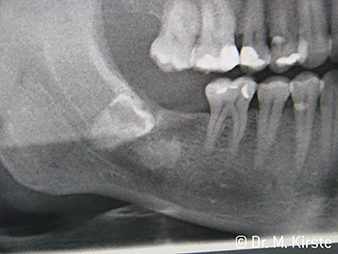

The dental handpieces WS-91 and WS-91 L G combine the advantages of surgical straight and contra-angle handpieces for the first time ever (Fig. 1). The extended angle between the shank and burr axis allows good access to the tooth row both buccally and occlusally (Fig. 4). Displaced teeth can be comfortably sectioned (Fig. 6 and 7). The dentist also has a significantly better view of the surgical site than with the instruments previously available. Dr. Mario Kirste from Frankfurt/Oder had this to say, “If I turn the contra-angle handpiece head slightly, I can work particularly quickly and safely in the retromolar region. The instrument has the potential to reconcile the contrasting positions taken up by the users of straight and contra-angle handpieces.” (Fig. 2-5)